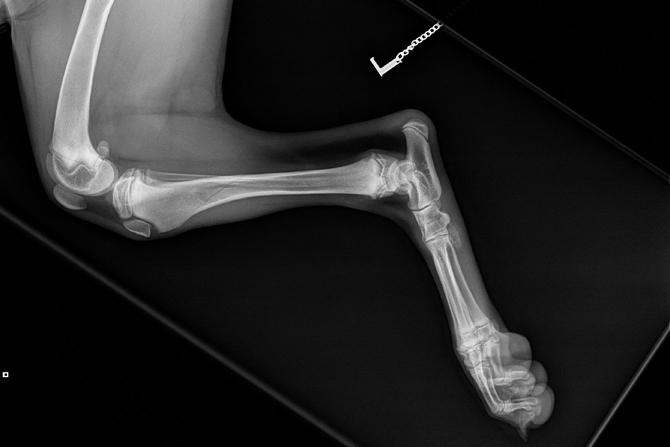

Takajalan röntgentutkimuksessa todettiin spiraalimaiselta vaikuttava murtumalinja sääriluun yläkolmannessa.

Jalka lastoitettiin ja Jitta sai kipulääkityksen. Jitta määrättiin häkkilepoon.